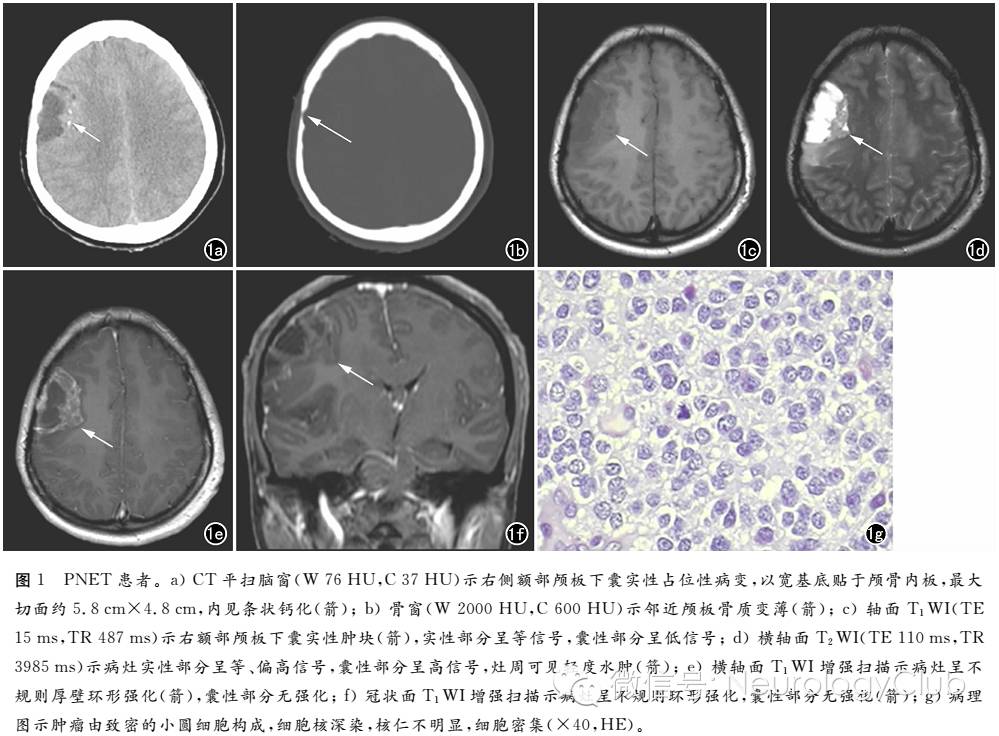

患者,女,37岁,外伤后行头颅CT检查发现右侧额叶病变(图1-2),为进一步检查收入我院行MRI检查 (图3-6)。既往史无特殊。查体:神志清,查体合作,对答切题。实验室检查无异常。CT检查:右侧额部颅板下囊实性占位性病变,最大切面约5.8cm×4.8cm,内见条状钙化,病灶以宽基底贴于颅骨内板并邻近颅板骨质变薄,侧脑室受压,中线结构轻度左移(图1a、b)。MRI检查:右额部颅板下囊实性肿块,实性部分呈等T1、长T2信号,灶周轻度水肿,增强扫描呈不规则厚壁环形强化(图1c-f)。

手术所见:右额下回后方一实性肿物,其基底为脑表面,大小约5cm×5cm,质软,色暗红,血供丰富,无包膜,见肿瘤突出脑皮层表面并向四周硬膜下腔延伸,肿瘤侵入脑内达3cm,与正常脑组织分界不清。病理检查:考虑为中枢神经系统原始神经外胚层肿瘤(图1g) 。 免疫组化:GFAP(++)、S100(+)、P53散在(+)、Vim(+)、EMA(-)、NF-L+H(-)、PCNA(+)、Ki67(平均约10%-30%,+)、CEA(-)、PR(-)、SYN(+)、CgA(-)、CD99(-)。

SPNET影像学特征为:①肿瘤多分布于额、颞叶,少数肿瘤位于枕叶,多呈类圆形或分叶状,病灶边界较清,不伴或仅伴轻度瘤周水肿;②肿瘤CT平扫呈稍高密度,MRI平扫表现为T1WI呈等或稍低信号,T2WI呈等或稍高信号,DWI上呈等高、高信号,CT或MRI增强扫描肿瘤实质常表现为均匀或不均匀明显强化;③肿瘤多伴有不同程度囊变,囊变多位于病灶周边;④瘤内可见出血、钙化及血管流 空,钙化少见(少于10%)。本例病灶位于额叶,呈囊实性,囊性部分位于病灶周边,灶内伴钙化,增强扫描实质部分明显不均匀强化,灶周水肿不明显,与文献报道基本一致。